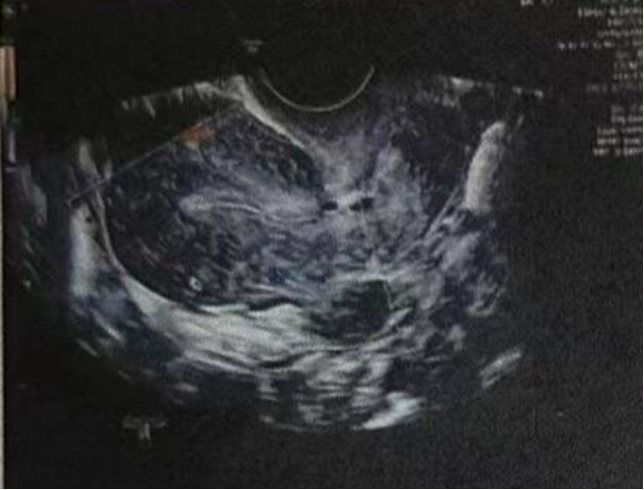

进入移植周期后,吉蒂亚医生启动内膜调理,通过温和的激素调节与内膜血供改善手段,帮助内膜逐步生长。最终内膜达到胚胎移植所需的理想厚度与形态,为后续着床筑牢子宫环境基础。

雌二醇:73.69 pg/mL

孕酮:0.38 ng/ml

子宫内膜厚度:4.6 毫米,子宫有瘢痕大小 0.76*0.19 厘米